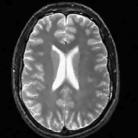

We study the performance of the proposed algorithms as a function of acceleration in the presence of noise in Fig. 3. We used a 512×512512512512\times 512 MRI brain image, sampled using a random sampling operator at different acceleration factors (R = 2.5, 4, 6, 8, 10 and 202020). The measurements were contaminated with complex white Gaussian noise of σ=10.2𝜎10.2\sigma=10.2. The PSNR and SNR as a function of accelerations of this experiment are plotted in Fig. 3, where we compare our method against DLMRI and TV. We observe that the proposed scheme provides a consistent improvement in the presence of noise.

The reconstructions of an ankle image from its 4 fold Cartesian undersampled Fourier data, corrupted with zero mean complex Gaussian noise with a standard deviation σ=10𝜎10\sigma=10, are shown in Fig. 5. This is a really challenging case since the 1-D downsampling pattern is considerably less efficient than the 2-D random pattern used in the previous experiment. We observe that the non-local algorithm provides better reconstructions than the other schemes. Specifically, the TV scheme results in patchy artifacts. The DLMRI scheme results in blurring and loss of details close to the heel. The details are relatively better preserved close to the finger since there are no structures above or below it that aliases to it. By contrast to the classical algorithms, the degradation in performance of the non-local algorithm is comparatively small. The quantitative comparisons of the algorithms on this setting using different images are shown in the top section of Table IV.

The reconstructions of a 256×256256256256\times 256 brain image from its radial samples acquired with a 40 spoke trajectory are shown in Fig. 6. The measurements are corrupted with zero mean complex Gaussian noise of standard deviation σ=18.8𝜎18.8\sigma=18.8. All methods result in loss of subtle image features since the acceleration factor and the noise level are high. We observe that the NLS scheme provides better recovery than the competing methods. The quantitative results in this setting for various MR images are shown in the bottom section of Table IV. We observe that the SNR improvement offered by NLS over the other methods are not as high as in the previous cases, mainly due to the considerable noise in the data and the high acceleration.

Finally, we show the recovery of four MR images from three fold radial under sampled data that is contaminated with zero mean complex Gaussian noise of standard deviation σ=10𝜎10\sigma=10. These experiments show that the NLS scheme can be used to obtain good quality reconstructions at moderate acceleration factors and noise levels.

TABLE IV: Quantitative comparison of the algorithms in the presence of noise. The top part shows the SNR of the reconstructions obtained from 4 fold Cartesian under sampled data, contaminated by zero mean complex Gaussian noise with standard deviation σ=10𝜎10\sigma=10. The bottom part shows the SNR of the reconstructions from radial under sampled data with 40 spokes, contaminated by zero mean complex Gaussian noise with standard deviation σ=18.8𝜎18.8\sigma=18.8. The quantitative results show that the proposed iterative NLS scheme provides consistently better reconstructions for the above cases.